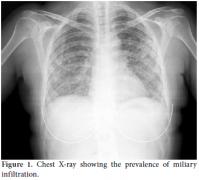

Drainage of the right temporal scalp nodular lesion yielded purulent material and showed Gram-positive bacilli. It later grew nocardial infection, but the specific species was unidentified because our hospital's laboratory could not make that determination. Daily doses of trimethoprim-sulfamethoxazole (TMP-SMX) 15 mg/kg were started. The azathioprine treatment was withdrawn, and the prednisolone dosage was decreased from 40 mg/day to 8 mg/day. In addition, the patient's blood cultures grew beaded, branching Gram-positive rods which were identified as nocardial infection, and high-dose ceftriaxone treatment (4 g/day) was added to the treatment regimen. Five days later, she suddenly developed dyspnea and a cough, and a chest X-ray showed prevalent miliary infiltration (Figure 1). Additionally, urgent thoracic computed tomography (CT) showed miliary nodular infiltration [miliary tuberculosis (TB)-type pattern that appeared to indicate an infection]. Therefore, a bronchoscopy was performed, but Gram staining of the broncoalveolar lavage (BAL) specimen showed no nuclear neutrophils, microorganisms, or acid-fast bacilli.